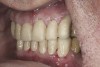

(9.) Preoperative right lateral, closed view.

Figure 9

(10.) Preoperative anterior, closed view. Note the end-to-end occlusion of the anterior teeth and the wear on the incisors and centrals resulting in no anterior or canine guidance.

Figure 10